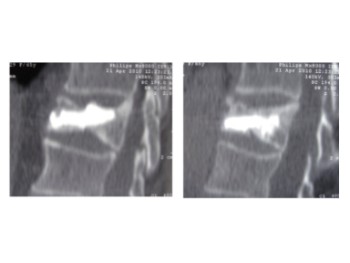

Comparación pre- y post-operatoria de una cifopastia cementada

Mujer, edad 55 años, Fractura aplastamiento derecho de L2

Antes 1

Después 1

Antes 2

Después 2